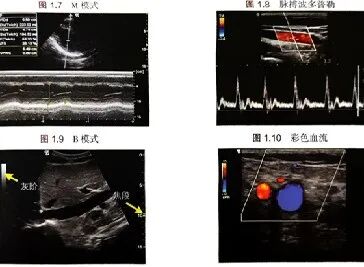

图3 不同的超声模式